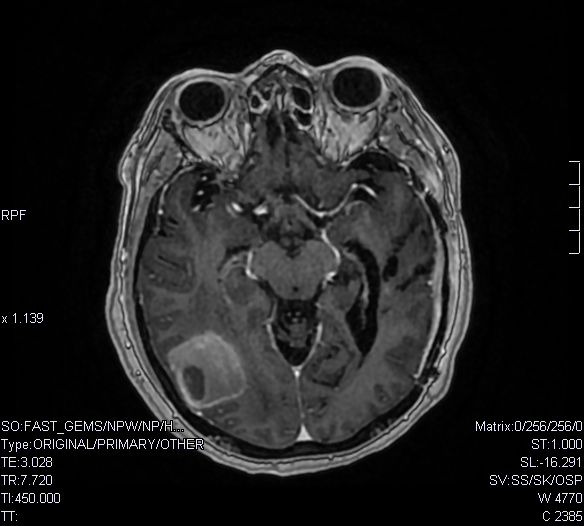

RM (T1)

HALLAZGOS RADIOLÓGICOS